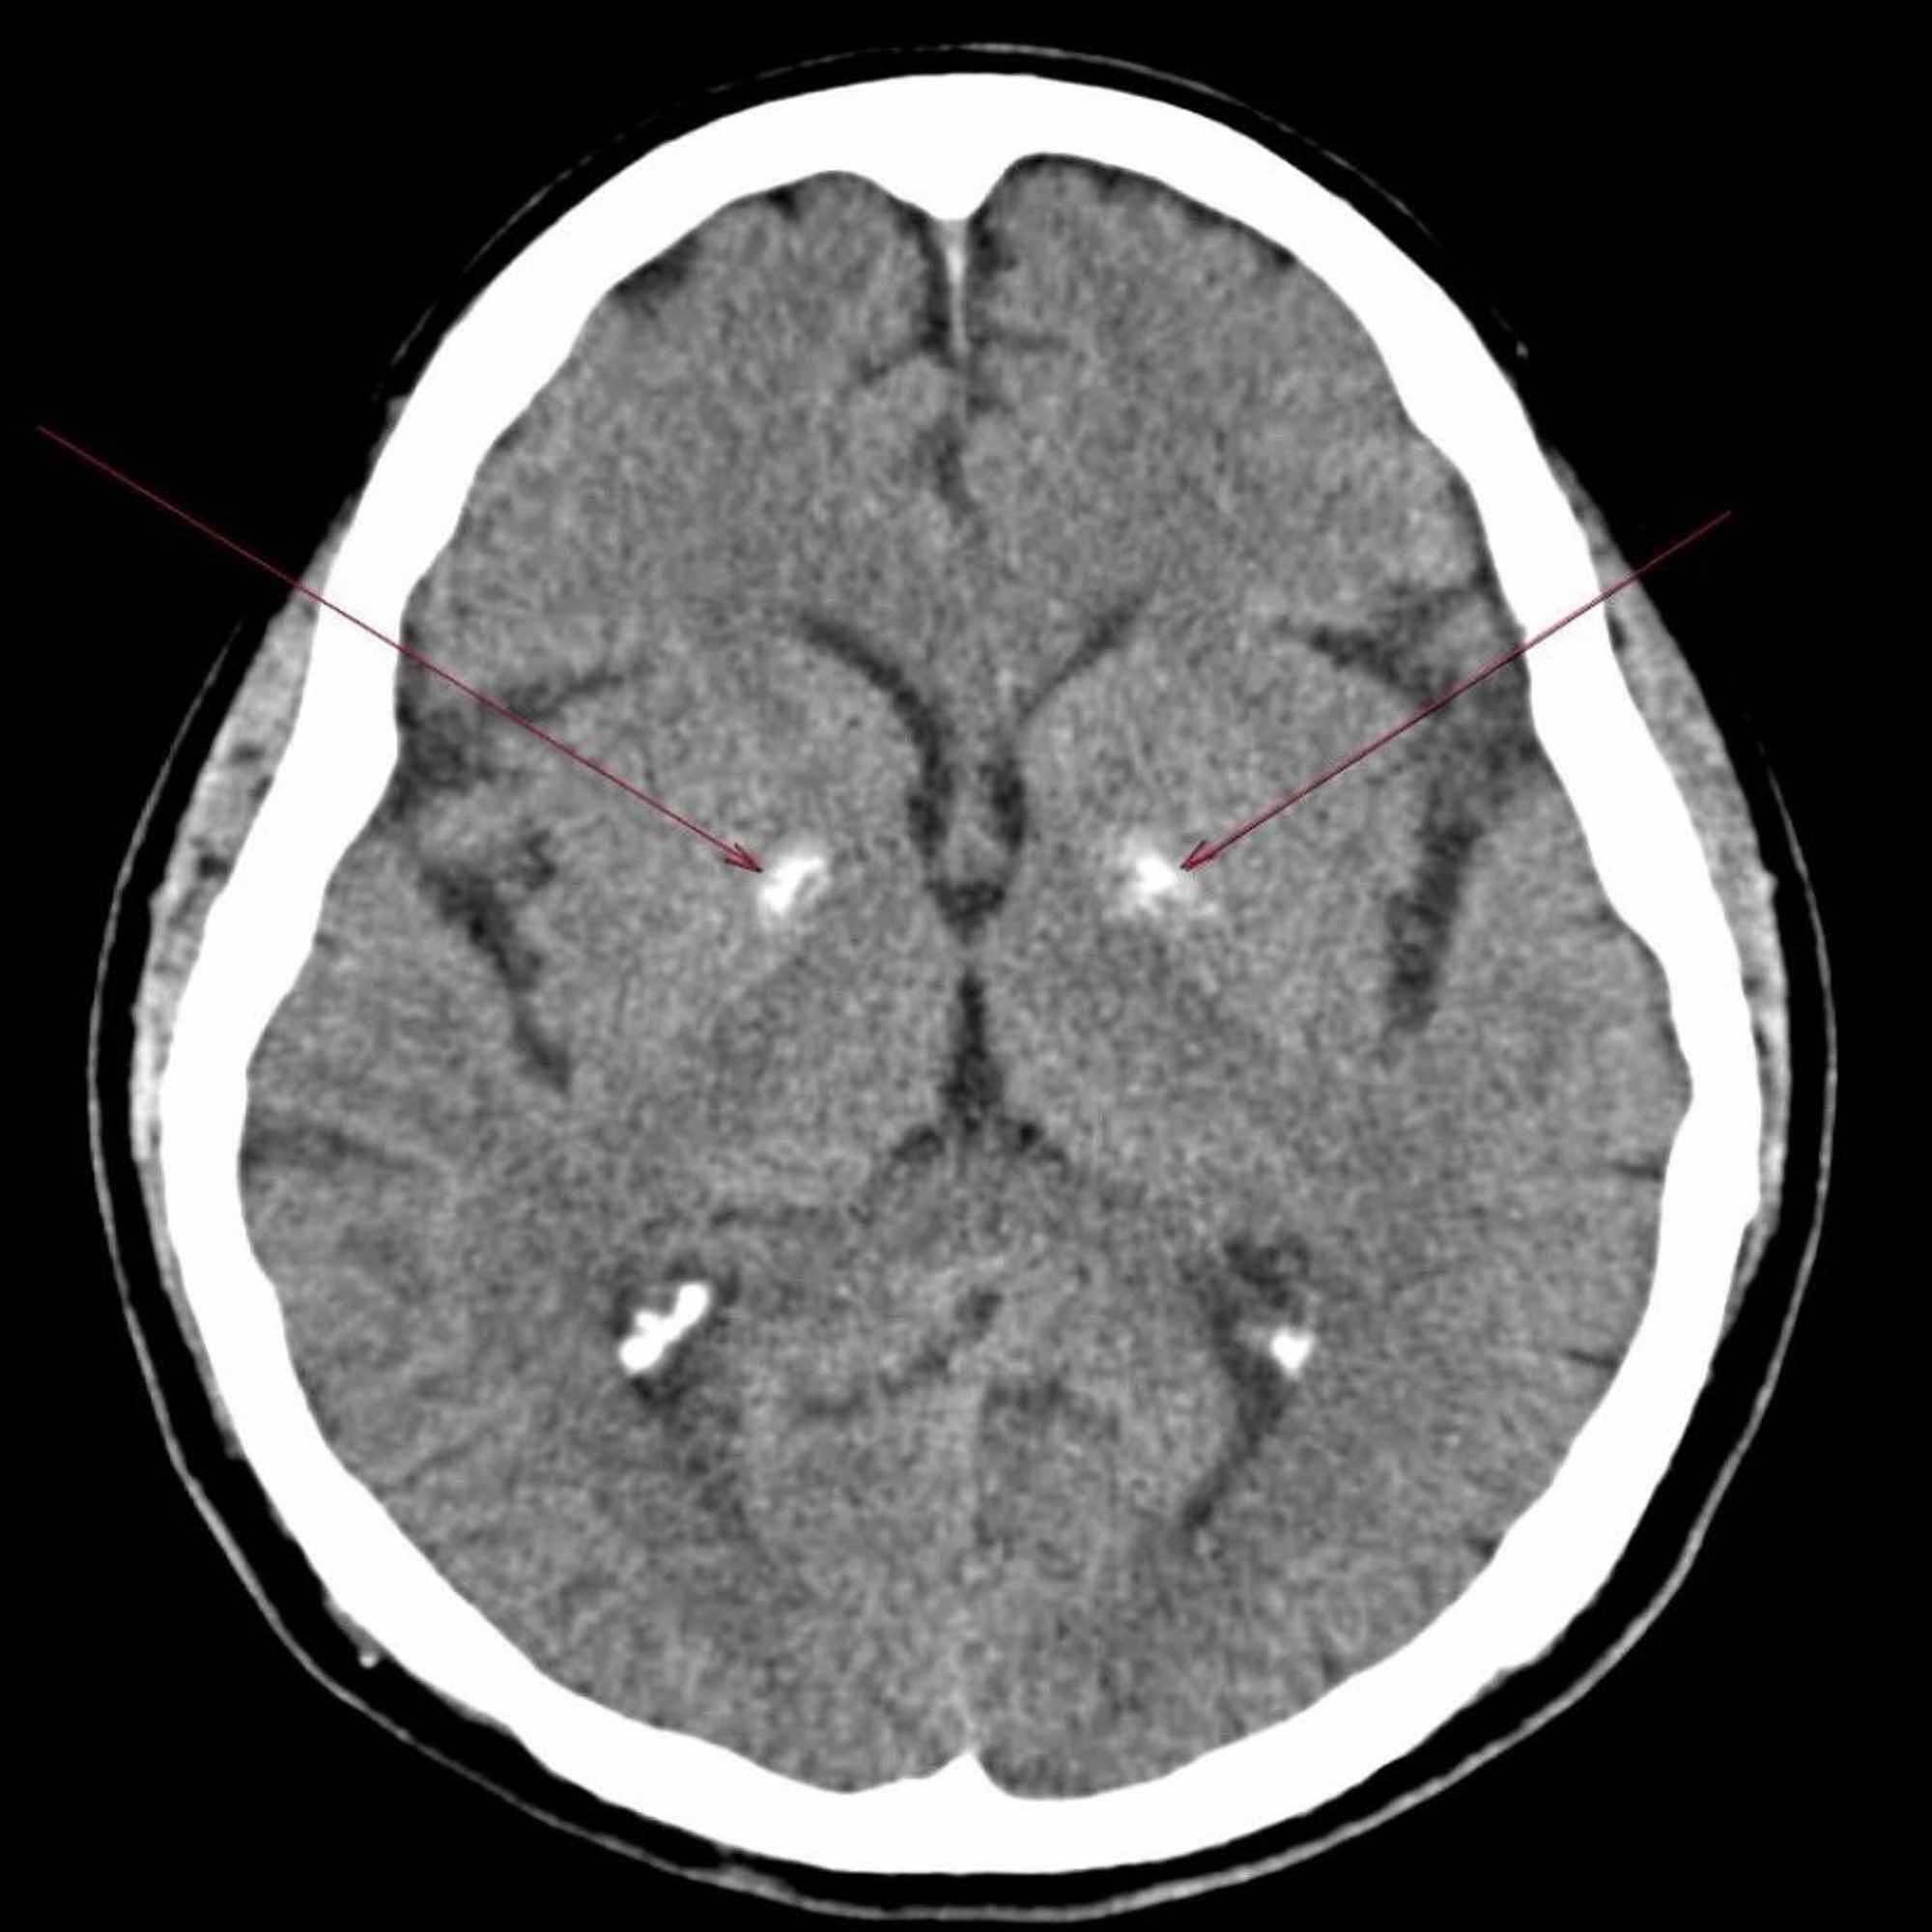

Image showing calcification over basal ganglia. Download Scientific Basal Ganglia Calcification Symptoms Dystonia (disordered muscle tone) chorea (involuntary rapid, jerky. fahr’s disease refers to when calcium deposits occur in the basal ganglia without an underlying condition or cause. learn about the inherited neuropsychiatric disorder that causes calcifications in the basal ganglia and other brain regions. Fahr disease is named after karl theodor fahr, a german neurologist who first reported the. Basal Ganglia Calcification Symptoms.

Brain CT scan shows bilateral calcification in basal ganglia Basal Ganglia Calcification Symptoms Symptoms of this disease include deterioration of motor functions and speech, seizures, and other. basal ganglia calcification is a rare neurodegenerative disorder occurring. learn about the inherited neuropsychiatric disorder that causes calcifications in the basal ganglia and other brain regions. fahr’s disease refers to when calcium deposits occur in the basal ganglia without an underlying condition or. Basal Ganglia Calcification Symptoms.